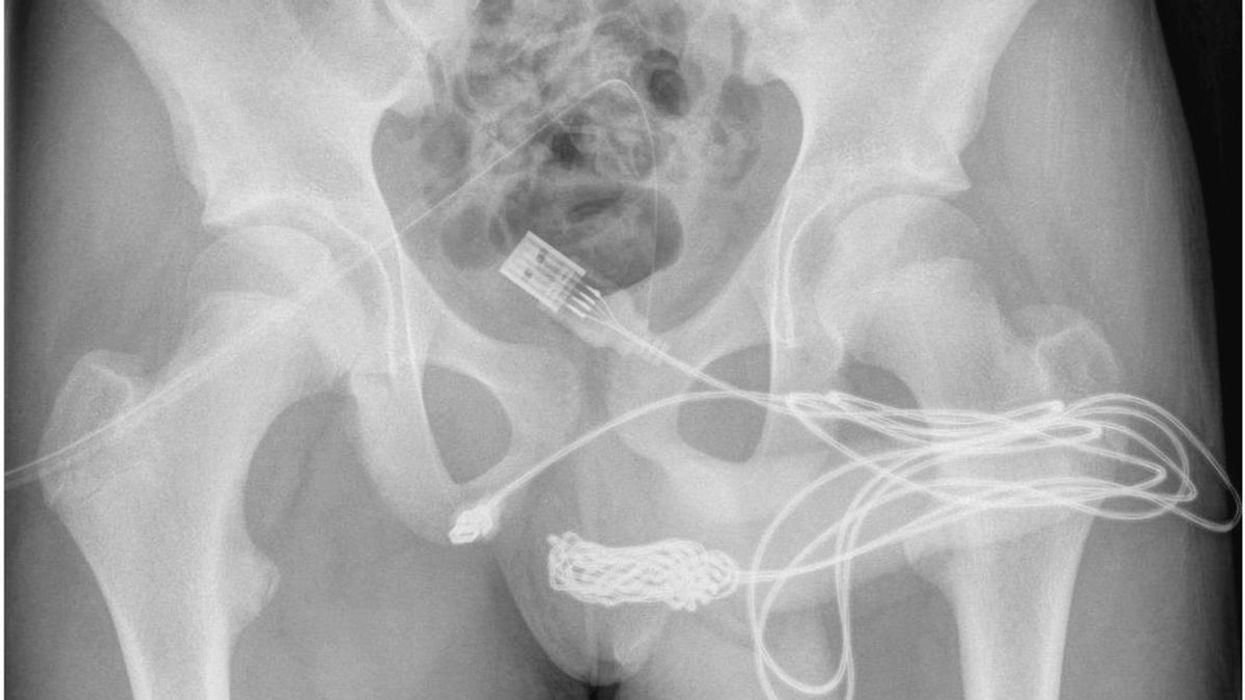

A 15-year-old boy from the UK reportedly required surgery after he got a USB cable stuck inside his penis.

Media reports state that he was taken to the hospital by his mother after he was unable to remove the USB cable, and after experiencing blood in his urine.

The boy was reportedly attempting to measure the inside of his penis with the cable in a bizarre form of "sexual experimentation" before it got knotted, thereby, making it impossible to take it out.

The boy had to reportedly undergo surgery because the doctors were unable to remove the cable with a metal rod due to the number of knots that had formed.

An insertion was made between his genitals and anus to allow access to the stuck cable, and catheters were then fitted.

Explaining the procedure, doctors wrote: "A longitudinal peno-scrotal incision over the palpable foreign body was made and careful dissection was undertaken through deeper tissues, splitting the bulbospongiosus muscle.

“Both ends of the wire were pulled out successfully through the external urethral meatus," the Mirror informs.

Doctors in the Science Direct report wrote, "The two distal ports of the USB wire were found to be protruding from the external urethral meatus whilst the middle part of the knotted wire remained within the urethra.